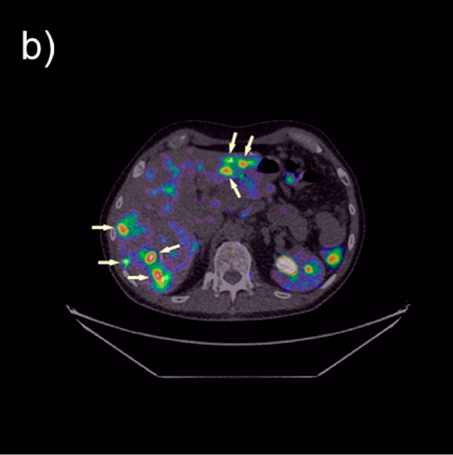

NCBJ OR POLATOM z dofinansowaniem na badania kliniczne w onkologii

Narodowe Centrum Badań Jądrowych Ośrodek Radioizotopów POLATOM otrzymał finansowanie z Agencji Badań Medycznych na realizację niekomercyjnego badania klinicznego w obszarze onkologii. Badania te dają nowe możliwości leczenia jednego z najbardziej agresywnych nowotworów piersi.

Nowoczesne nano-radiofarmaceutyki do diagnostyki i terapii

Dr Karolina Zajdel z Narodowego Centrum Badań Jądrowych otrzymała w ramach programu SONATINA Narodowego Centrum Nauki finansowanie niezwykłego projektu. Wraz z zespołem stworzy ona uniwersalne nano-radiofamaceutyki, które umożliwiały będą zarówno wykrywanie, jak i selektywne niszczenie komórek nowotworowych.

Naukowcy NCBJ zbadają możliwość wykorzystania wielofotonowej tomografii PET dla obrazowania przemysłowego

Pozytonowa Tomografia Emisyjna jest wykorzystywana przede wszystkim w medycynie. Właściwości tej techniki mogą jednak okazać się przydatne również w zastosowaniach przemysłowych. Takim wykorzystaniem techniki PET zajmują się specjaliści Departamentu Układów Złożonych NCBJ w ramach projektu IMPET, uzyskanego w programie First Team FENG Fundacji na rzecz Nauki Polskiej.